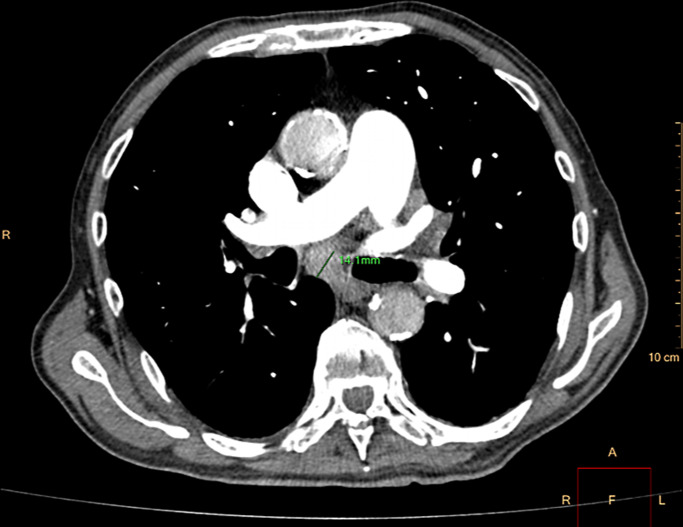

Case presentation: An 81-year-old male with a history of age-related macular degeneration presented with acute onset of pain and restricted movement in his left eye. Computed tomography imaging revealed an osteolytic lesion in the left sphenoid bone, causing reactive myositis. Further systemic evaluation identified a left renal mass with evidence of pulmonary and skeletal metastases. A core needle biopsy confirmed the diagnosis of metastatic renal cell carcinoma. Given the advanced disease stage, the patient was managed with palliative treatment. Despite medical interventions, he succumbed to the disease 6 months after symptom onset.